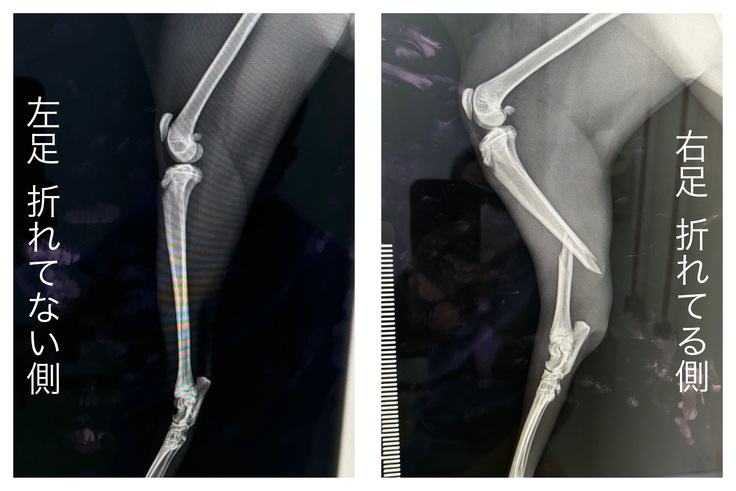

再度検査を受けた結果、右後ろ足の脛骨・腓骨の骨折と診断をうけ、手術と入院が必要だと判断されました。以下がレントゲンの写真になります。